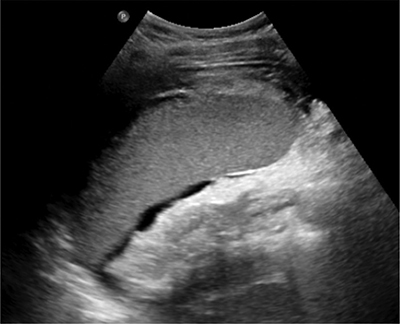

Figure 1

Abdominal ultrasound shows splenomegaly and a perisplenic, layered fluid collection.